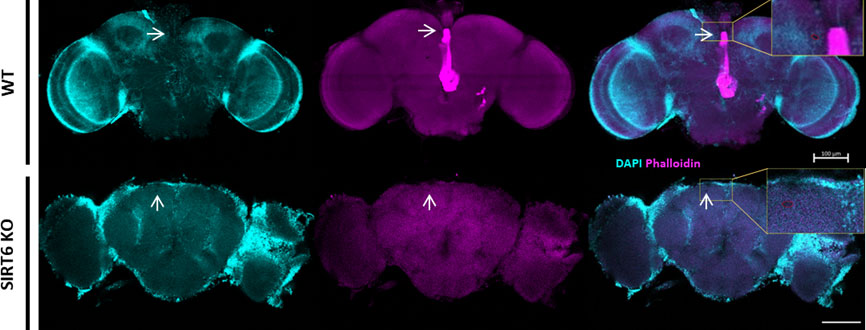

البروفيسور ديبرا تويبر وزملاؤها في جامعة بن غوريون في النقب لقد كشفت عن تفسير بيولوجي محدد لهذا الاضطراب. يشير عملهم إلى غياب البروتين المرتبط بطول العمر المعروف باسم Sirtuin 6 (SIRT6) كعامل رئيسي في فقدان التحكم الأيضي الطبيعي.

وباستخدام التجارب على الخلايا وذبابة الفاكهة والفئران، أظهر الباحثون أن SIRT6 يلعب دورا فعالا في توجيه نشاط الجينات، بما في ذلك الجينات مثل (على سبيل المثال، TDO2، AANAT). عندما يكون SIRT6 مفقودًا، فإن هذا التنظيم الجيني يحول استقلاب التربتوفان نحو مسار الكينورين، والذي يرتبط بالتأثيرات السمية العصبية، مع تقليل إنتاج الناقلات العصبية التي تدعم وتحمي وظائف المخ بشكل طبيعي.